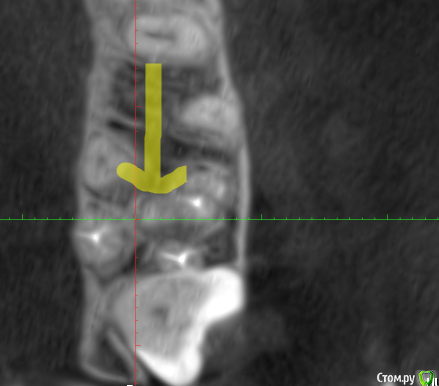

It'sGeorgy Опубликовано 11 декабря, 2019 Поделиться Опубликовано 11 декабря, 2019 (изменено) Всем здравствуйте! Слишком много проблемных пазух сыпется на меня в последнее время. Пациентку в лицо впервые увижу в пятницу, обратилась в клинику с жалобами "пол головы болит, сделайте что-то, мне в отпуск через месяц" . По телефонному разговору удалось разузнать: лежала в неврологии 3 месяца назад, где обострился гайморит. Там отправили к ЛОРами, те назначили антибиотики и сказали делать "кукушку", там же сделали КТ(в приложениях). После этого, пошла по ДМС к другому ЛОРу, показала КТ. Сказали, причина в восьмерке. Восьмерка полностью ретенирована(Со слов пациентки, опять же, сам не видел еще). Корень в пазухе(?). - прикрепленное 1.Рядом находится 2.7 с незапломбированным мб2 - прикрепленное 2. И недопломбированным небным корнем + воспаление на этом корне. - прикрепленное 3.Пазуха - прикрепленное 4. https://cloud.mail.ru/stock/bky4cB7brg4DmMjaY7NSGR7y - KT + MPT. Открывается винраром. На перелечивание 2.7 зуба пациентка может не согласиться. Удалять ли 2.7 зуб? Может ли ТОЛЬКО полностью ретинированная восьмерка вызвать подобное состояние пазухи или искать что-то еще? Изменено 11 декабря, 2019 пользователем It'sGeorgy Ссылка на комментарий

krokomot Опубликовано 11 декабря, 2019 Поделиться Опубликовано 11 декабря, 2019 Лор патология на лицо, соустье не рабочее 100%, да мб2 пустой, но думаю не в нем дело. Ваше дело маленькое, удалить восьмой на мой взгляд он в полуретенции, пролечить седьмой, дальше отправляйте к лорам, пусть лечат. 2 Ссылка на комментарий